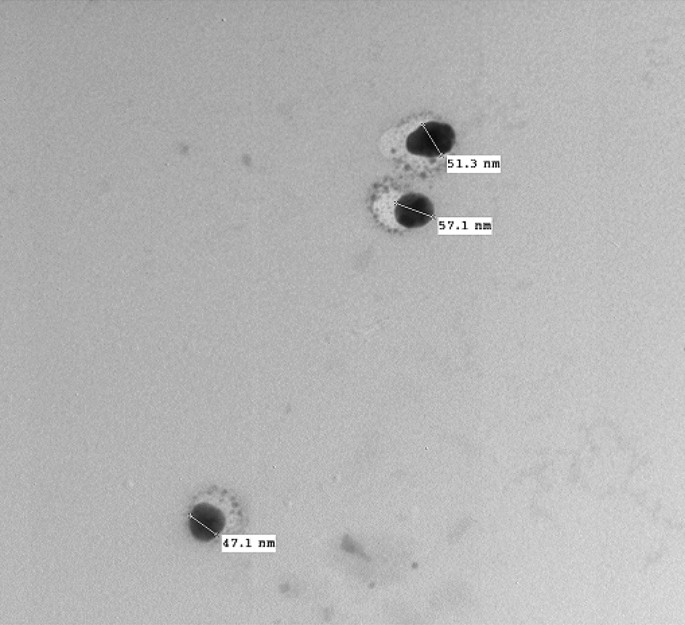

In the present study, Cur-NE was set according to the method of Ben et al. and Kesisoglou and Panmai23,24,25 and characterized using several techniques. The shape and size of Cur-NE were observed by TEM (Fig. 3). The round nanoparticles in the TEM image are evenly distributed, not aggregated, and range in diameter from 45 to 60 nm. The dynamic light scattering (DLS) measurement shown in Fig. 4a supports this finding. The size of Cur-NE is centered at 459 nm, (PDI = 0.604) with a reasonably narrow distribution but appears to be higher compared to TEM due to the interference of the dispersant to the hydrodynamic diameter. The potential analyzer was used to determine the electro-kinetic surface potential for Cur-NE (Fig. 4b). The value of zeta potential for Cur-NE is (− 16 mV ± 1.2). This result revealed that the particles were stable and evenly spread. These results matched those of Paolino et al.40, who stated that particles with a high negative or positive zeta potential are suspended. Because the particles are opposing each other, there will be no desire for them to stick together.

Transmission electron microscope (TEM) image of curcumin loaded in nano emulsions (Cur-NE).